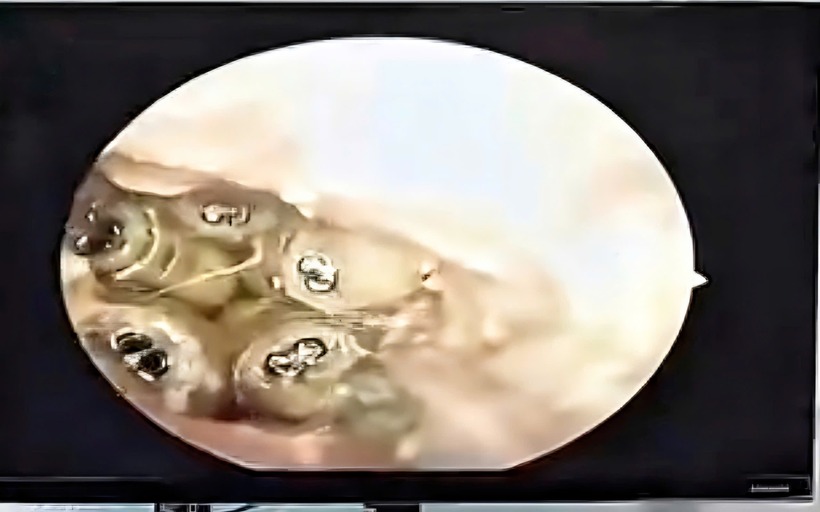

5 con giòi trong tại của bệnh nhân. Ảnh: Sức khoẻ & Đời sống.

Trước đó, ngày 23/10, một nữ bệnh nhân 48 tuổi được người nhà đưa đến Bệnh viện đa khoa Khánh Hòa trong tình trạng tai sưng to, chảy dịch và đau dữ dội. Khi tiến hành soi tai, bác sĩ bất ngờ phát hiện nhiều vật thể màu trắng đang ngọ nguậy bên trong ống tai.

Sau khi hút sạch dịch trong ống tai, các bác sĩ đã gắp ra 5 con giòi còn sống cùng xác một con côn trùng nằm sát màng nhĩ. Theo nhận định của bác sĩ, do bệnh nhân không thể tự chăm sóc bản thân, trong quá trình sinh hoạt có thể côn trùng đã chui vào tai, làm tổ và đẻ trứng, sau đó trứng nở thành giòi.